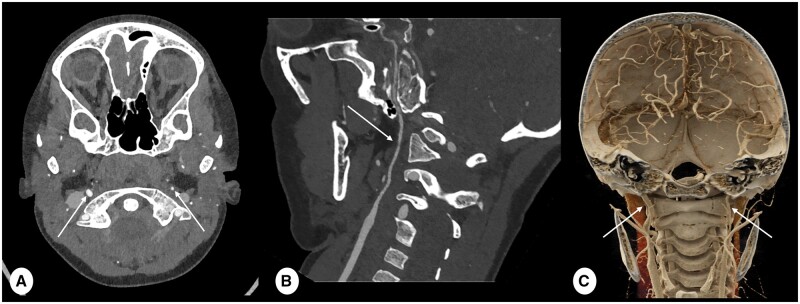

Recent advancements in CT technology have introduced a revolutionary innovation to practice known as the Photon-Counting detector (PCD) CT imaging. The pivotal hardware enhancement of the PCD-CT scanner lies in its detectors, which consist of smaller pixels than standard detectors and allow direct conversion of individual X-rays to electrical signals. As a result, CT images are reconstructed at higher spatial resolution (as low as 0.2 mm) and reduced overall noise, at no expense of an increased radiation dose. These features are crucial for paediatric imaging, especially for infants and young children, where anatomical structures are notably smaller than in adults and in whom keeping dose as low as possible is especially relevant. Since January 2022, our hospital has had the opportunity to work with PCD-CT technology for paediatric imaging. This pictorial review will showcase clinical examples of PCD-CT imaging in children. The aim of this pictorial review is to outline the potential paediatric applications of PCD-CT across different anatomical regions, as well as to discuss the benefits in utilizing PCD-CT in comparison to conventional standard energy integrating detector CT.